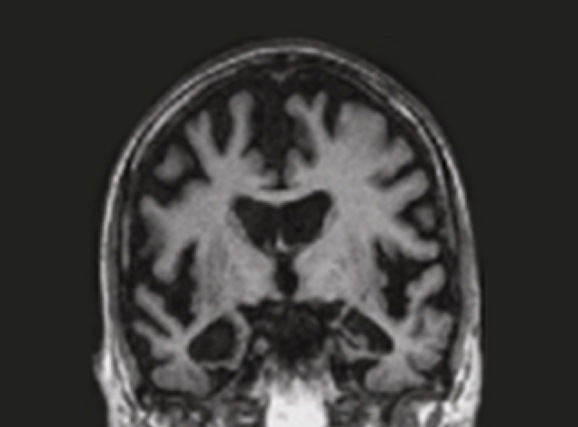

정상 뇌 영상 치매 환자 뇌 영상

정상뇌

치매 환자